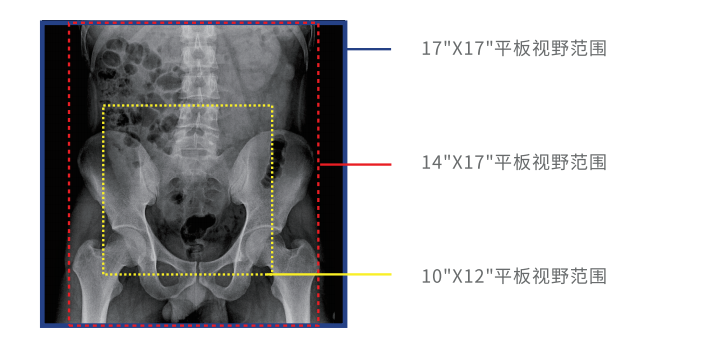

大幅面高清成像

動(dòng)態(tài)DR采用17 英寸×17 英寸方形動(dòng)態(tài)成像,臨床操作醫(yī)生可以在一個(gè)大幅面下觀察診斷,當(dāng)看到病變部位時(shí),配合實(shí)時(shí)點(diǎn)片技術(shù),能夠很好地捕捉到病變點(diǎn),也大大縮短了檢查時(shí)間,與圓形成像的傳統(tǒng)胃腸機(jī)相比在臨床上具有巨大優(yōu)勢(shì)。